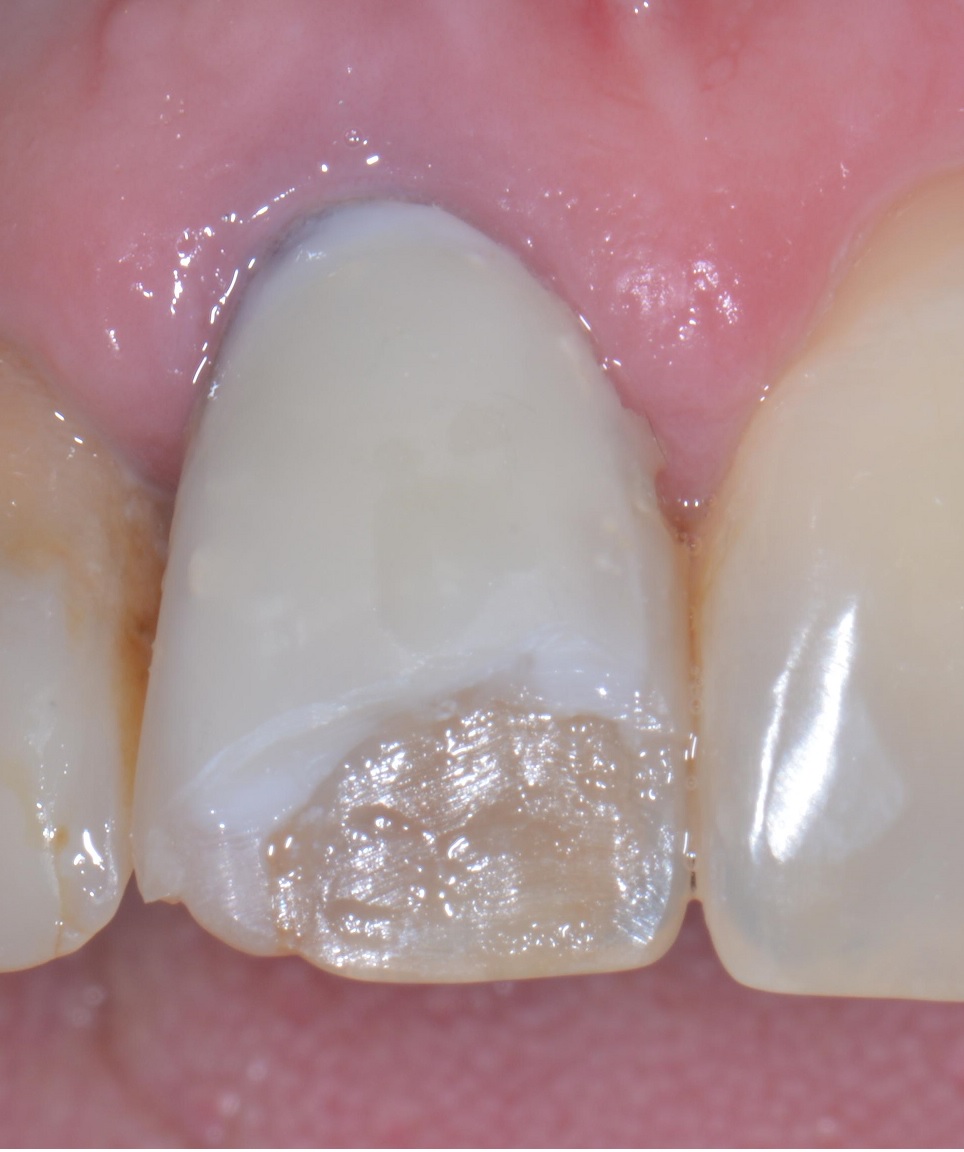

Ma l’hai vista la foto di prima?! Forse non ti è chiaro…cerco di spiegarti meglio…

Devo soffermarmi su cosa non vada in questo lavoro? Ma solo io ho pazienti che non accetterebbero mai un lavoro simile? Per far pagare una merdata simile 250 euro in nero ci va un bel coraggio! Ma come dormi la notte? Ah, lo so, su un cuscino e un materasso imbottito di banconote belle soffici…

Il dente della signora aveva un perno dentatus a vista dal lato palatino, era discromico, è stato lasciato il vecchio composito sotto la nuova pregiata faccetta, ha il colore sbagliato e andava fissato un appuntamento di revisione per decenza prima di chiedere 250 euro. E poi il 21 ha una carie, il 12 è devitalizzato e deve contenere all’interno una di quelle schifezze di paste di medicazione nere. Il 15 e il 16 anche solo facendo aprire la bocca alla paziente si vede che hanno qualcosa che non va e la paziente mi ha detto “ah, sì, quello mi ha fatto malissimo e il dentista ha detto che la prossima volta vediamo un po’ se si riesce a recuperare, ho già un appuntamento ma a questo punto non vado più e vengo da voi…”